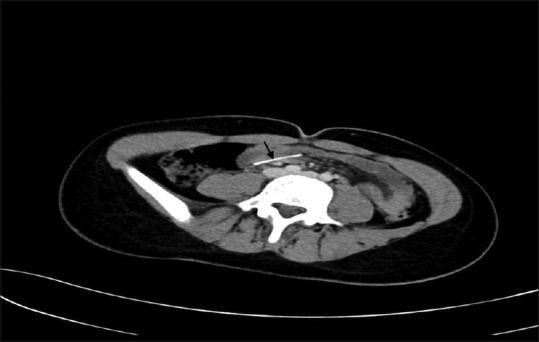

В публикации[1] доктора из Саудовской Аравии представлен опыт диагностики и лечения 13-летней пациентки, которая была госпитализирована через 48 часов после того, как случайно проглотила булавку для платка. Она жаловалась на жар и умеренную боль в животе, тошноту. При обследовании зафиксированы: температура тела — 38,6 °С, артериальное давление — 102/60 мм рт. ст., частота сердечных сокращений в покое — 118 ударов в минуту, частота дыхания — 20 дыхательных движений в минуту. При пальпации живот мягкий, не напряжен. Результаты анализа крови: гемоглобин — 125 г/л, лейкоциты — 7,4 × 109 клеток/л. При рентгенографии органов брюшной полости в тонкой кишке обнаружена булавка, это подтвердила и КТ живота (рис. 1). В ходе динамического наблюдения отмечено продвижение булавки в толстую кишку (рис. 2). В течение 4 дней, пока ИТ оставалось в восходящей ободочной кишке, пациентка продолжала жаловаться на боли в животе. В связи с этим ей была назначена колоноскопия, которая обнаружила булавку в восходящей ободочной кишке, в нескольких сантиметрах от слепой кишки. Повреждений слизистой оболочки зафиксировано не было, булавка была успешно извлечена с помощью щипцов «крысиный зуб» (рис. 3).

Рисунок 2.